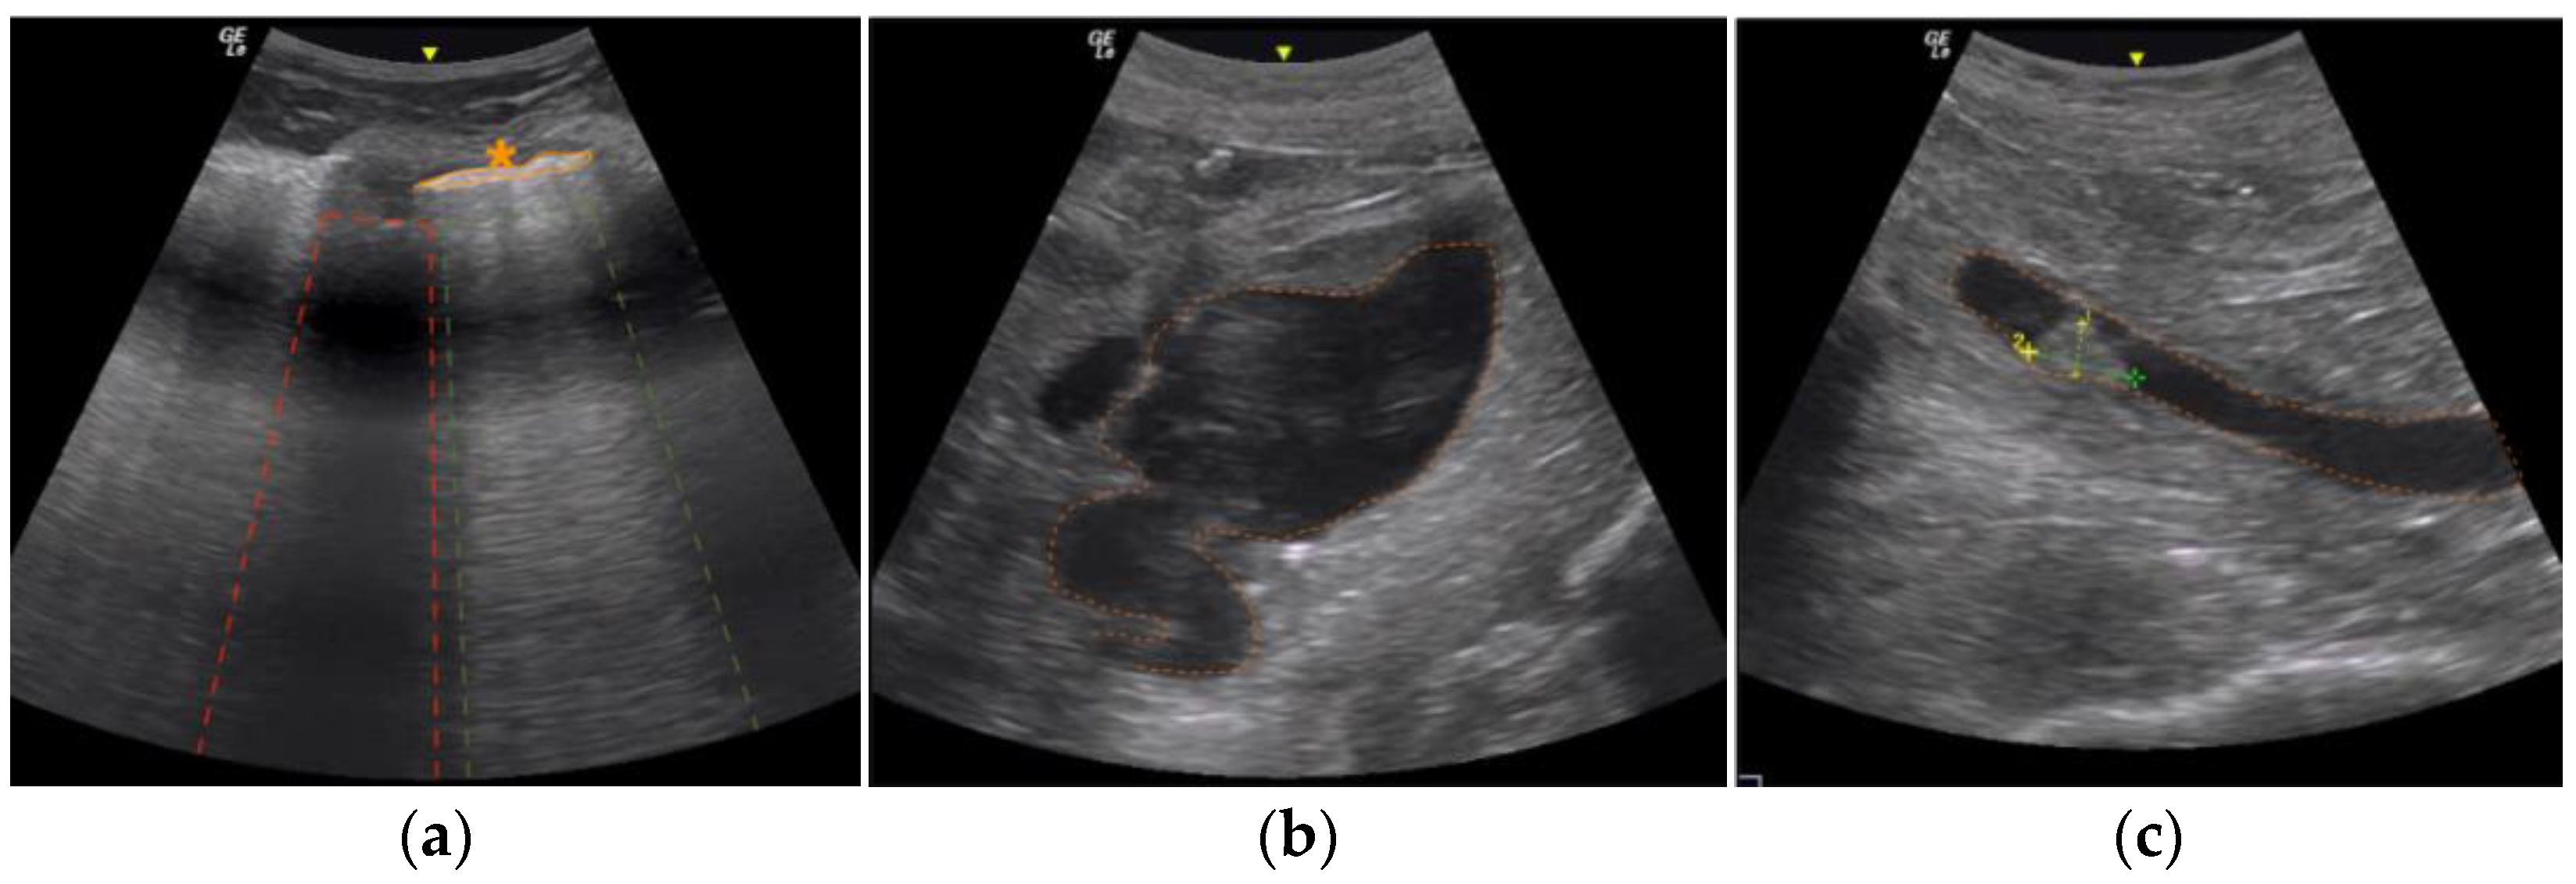

3.1. Post Mortem Ultrasound Findings